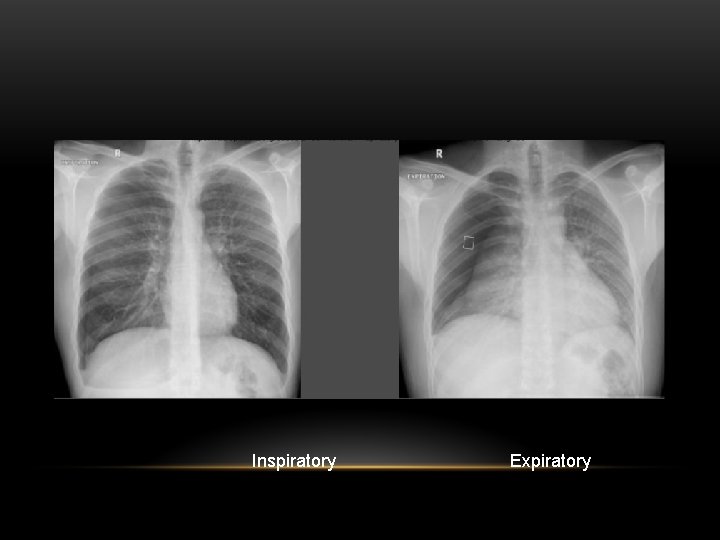

Inspiratory Expiratory